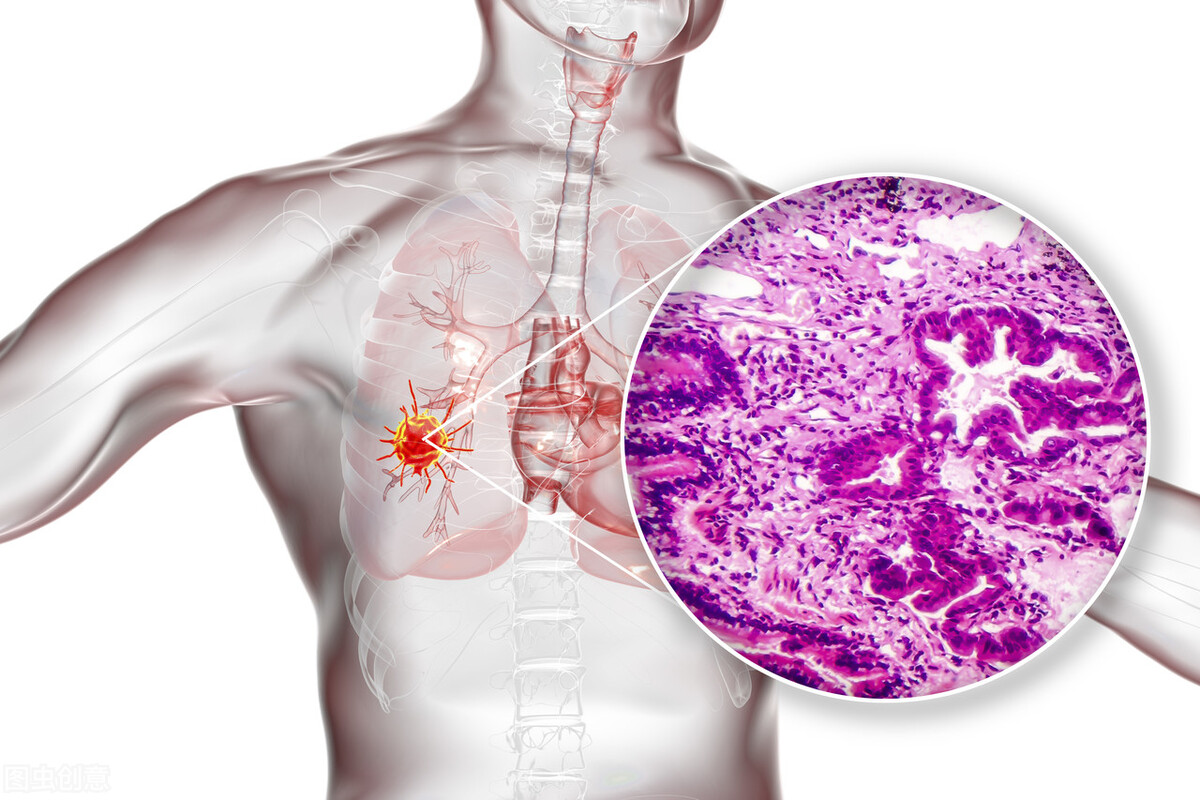

3.肺癌:肺癌,因为医学证明,肺癌的病灶是能影响到人们的肌肉酸痛的,仿佛与神经痛或关节疼痛的症状相似。早期肺癌病人有许多身体症状,如久治不愈的咳嗽、咯血与胸肩部隐痛;慢性咳嗽者咳嗽性质改变,转为刺激性干咳、痰中带血;某个肺叶、肺段反复发生肺炎。